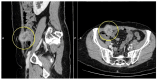

Cervical cancer is the fourth most common cancer in women, the highest mortality being found in low- and middle-income countries. Abdominal parietal metastases in cervical cancer are a very rare entity, with an incidence of 0.1-1.3%, and represent an unfavorable prognostic factor with the survival rate falling to 17%. Here, we present a review of cases of abdominal parietal metastasis in recent decades, including a new case of a 4.5 cm abdominal parietal metastasis at the site of the scar of the former drain tube 28 months after diagnosis of stage IIB cervical cancer (adenosquamous carcinoma), treated by external radiotherapy with concurrent chemotherapy and intracavitary brachytherapy and subsequent surgery (type B radical hysterectomy). The tumor was resected within oncological limits with the histopathological result of adenosquamous carcinoma. The case study highlights the importance of early detection and appropriate treatment of metastases in patients with cervical cancer. The discussion explores the potential pathways for parietal metastasis and the impact of incomplete surgical procedures on the development of metastases. The conclusion emphasizes the poor prognosis associated with this type of metastasis in cervical cancer patients and the potential benefits of surgical resection associated with systemic therapy in improving survival rates.